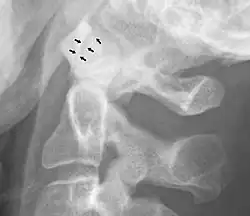

Osteoarthritis may occur at the atlanto-axial joint.[5] This involves classic pathophysiology, such as loss of articular cartilage, osteophytes visible with radiography, and bone thickening with a narrow joint space.[5] Conservative management is usually effective, involving analgesics.[5] Surgery may be used in severe cases, and may have good outcomes.[5]

Abnormal widening

A widening of the atlanto-axial joint, as measured between the posterior surface of the anterior arch of atlas and the front of the odontoid process, indicates an injury to the transverse atlantal ligament.[6] Normally, this atlanto-dental distance is less than 2 mm, sometimes a maximum of 3 mm is accepted in men and 2.5 mm in women.[6]